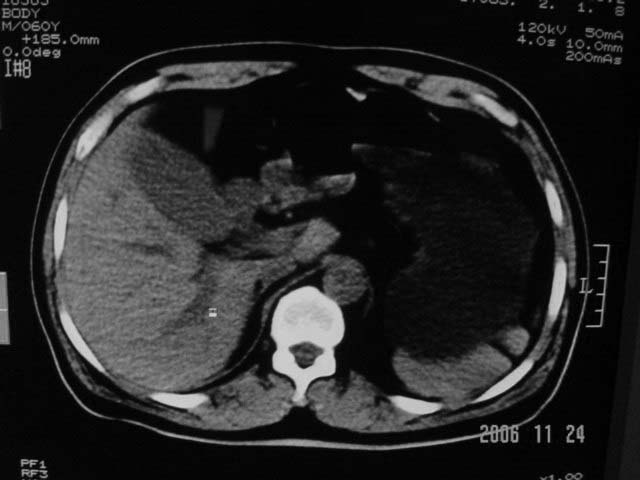

标题: CT5395:男、60岁,皮肤、巩膜黄染伴上腹部疼痛20天 [打印本页]

标题: CT5395:男、60岁,皮肤、巩膜黄染伴上腹部疼痛20天

感觉不是结石可能,与上一层面联系应该是门脉区影像,图像显示不佳,胆总管显示不清[特别是胰头以上段],目前影像只能说肝内外胆管扩张,胰管扩张,胆囊扩大。提示胆总管远端梗阻。可考虑肿瘤或结石所致

请结合临床及进一步检查。

肝内外胆管及胰管均示有扩张,胆囊增大.提示胆总管远端梗阻,可考虑肿瘤或结石或肿瘤伴结石,建议强化扫描

考虑胆总管结石致肝内外胆管扩张,胆囊增大,不像是肿瘤

支持胆总管下段结石并肝内外胆管扩张。